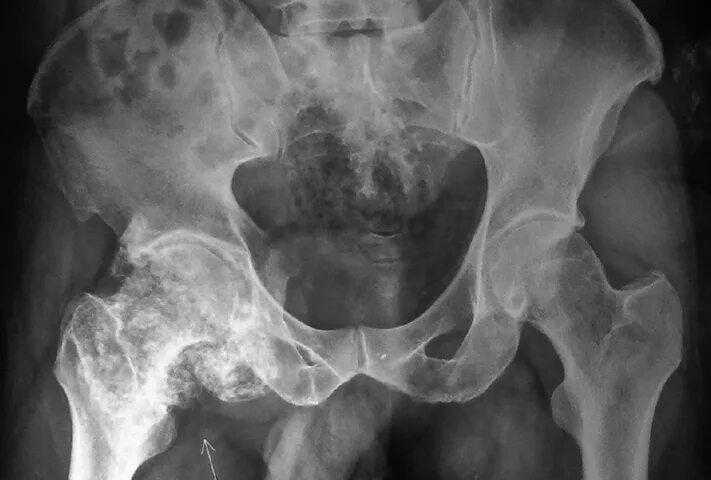

Анкилоз тазобедренного сустава